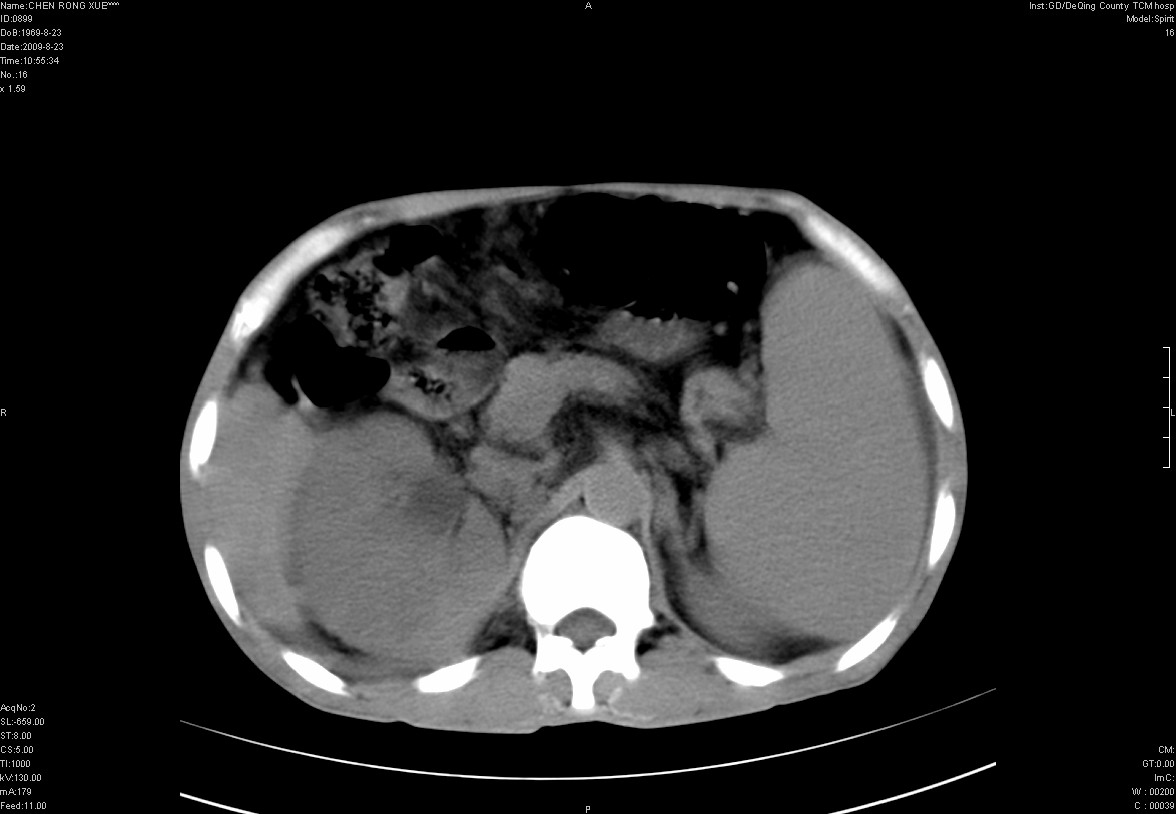

以下是引用zxl51642在2009-8-23 12:56:00的发言:[br]1、肝硬化、脾大;2、慢性胆囊炎;3、右肾占位并右侧腰大肌受侵,考虑恶性可能性大,建议增强扫描进一步检查。

以下是引用qiuleiyu在2009-8-23 15:17:00的发言:[br]1、慢性肝病,肝硬化,脾大,门脉高压。胆囊小结石。[br]2、右肾明显肿大,伴片状低密度灶,累及右侧腰大肌,肿瘤及炎症性病变皆有可能大,建议增强。

以下是引用zjzjr在2009-8-23 17:42:00的发言:[br]1、慢性肝病,肝硬化,脾大,门脉高压。胆囊小结石。[br]右肾脓肿波及肾周,建议增强

以下是引用dyqct在2009-8-23 16:53:00的发言:[br][quote]以下是引用qiuleiyu在2009-8-23 15:17:00的发言:[br]1、慢性肝病,肝硬化,脾大,门脉高压。胆囊小结石。[br]2、右肾明显肿大,伴片状低密度灶,累及右侧腰大肌,炎症性病变可能,建议增强。